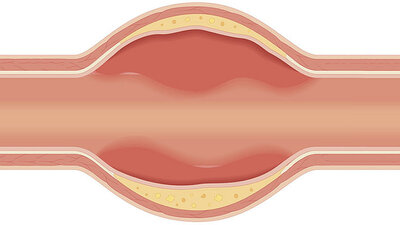

Arteriosklerose – gefährlicher Engpass

Gefäßverkalkung kann zu Herzinfarkt, Schlaganfall und anderen Durchblutungsstörungen führen. Mehr zu Ursachen, Therapie und Vorbeugung. zum Artikel

Makroangiopathie

Makroangiopathien sind Schädigungen der großen Blutgefäße. Sie können bei Diabetes eine Folge von erhöhten Blutzuckerwerten sein zum Artikel